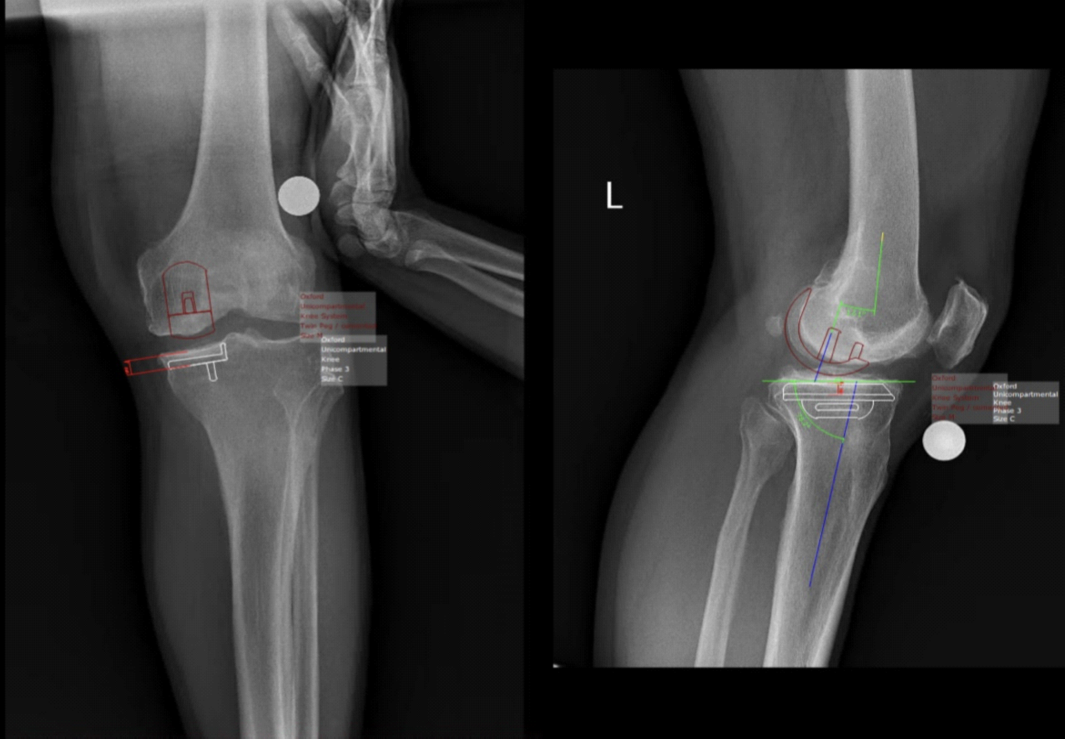

临床方面,洛阳中心医院骨科在王伟教授的大力支持下,膝关节骨性关节炎阶梯化治疗、髋膝关节置换术前规划、机器人导航、髋膝关节翻修方面实现了零的突破,并逐渐做大、做强,尤其是单髁置换(50多例)、术前规划(50余例)等技术领先豫西地区。借助国家区域医疗中心建设平台,由王伟教授牵头、组织,洛阳中心医院与西安交大二附院针对骨科疑难病例进行线上讨论,并由西交大二附院骨科教授进行线上授课,受到洛阳中心医院骨科同仁的一致好评。